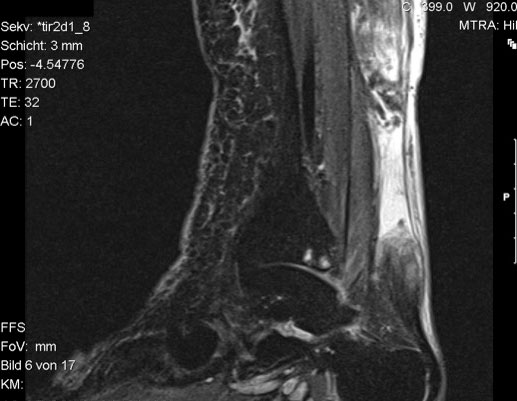

Abbildung 4a

Abbildung 4b

Der geübte Untersucher kann anhand des seitlichen Röntgenbildes die Diagnose einer Achillessehnenruptur stellen. Die Konturen des Kager-Dreiecks – gebildet von der ventralen Begrenzung der Achillessehne, der posterioren Tibiakante und der kranialen Kalkaneuskortikalis – verstreichen im Rupturfall (Kager 1939). Die MRT- Diagnostik spielt für die Primärdiagnostik der frischen Achillessehnenruptur eine untergeordnete Rolle und ist im Normalfall nicht notwendig. Anders verhält es sich bei den chronischen Rupturen. Hier ist die MRT ein wichtiges Diagnostikum insbesondere in Hinblick auf die Beurteilung der Sehnen- und Muskeldegeneration (Abb. 6).

Abbildung 6

Neben der strukturellen Wiederherstellung der Sehne ist die funktionelle Beurteilung des Muskels von entscheidender Bedeutung. Ist es bereits zu einer Degeneration der Muskeln gekommen, kann ein gutes funktionelles Ergebnis, trotz subtiler Sehnenrekonstruktion, nicht erreicht werden. Die Arbeitsgruppe um Hoffmann et al. 13 konnte in ihrer Arbeit zeigen, das es - ähnlich wie bei Patienten mit chronischen Supraspinatusrupturen - zu fettigen Degenerationen und Ödemen der Muskulatur kommt, die im MRT nachweisbar sind. Wir empfehlen die MRT- Untersuchung des gesamten Unterschenkels und nicht nur die rupturnahen Bereiche. Des Weiteren lässt die MRT eine Beurteilung der Degeneration der umliegenden Sehnenanteile zu. Die Computertomographie sollte nur in Ausnahmefällen zum Ausschluss von Begleitverletzungen (Abb. 7) durchgeführt werden und gibt uns sonst keinen weiteren Informationsgewinn.